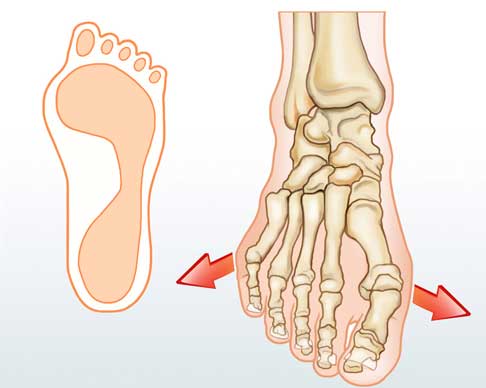

Bei einem Spreizfuß (lat. Pes transversoplanus) ist das Fußquergewölbe eingesunken. Die Mittelfußknochen weichen fächerförmig auseinander, statt gerade nach vorne zu zeigen. Der Vorfuß ist stark verbreitert, sodass Betroffene Schwierigkeiten haben, passende Schuhe zu finden. Auslöser für die Spreizfuß-Fehlstellung können Bindegewebsschwächen, Übergewicht und falsches Schuhwerk sein.

Im Gegensatz zum Senkfuß oder Plattfuß, bei dem das Fußlängsgewölbe abgeflacht ist, senkt sich beim Spreizfuß das vordere Quergewölbe des Fußes ab und der Vorfuß verbreitert sich. Das führt zu einer veränderten Belastung der Vorfußknochen. Auch die 2. bis 4. Mittelfußknochen werden massiv überlastet. Mit zunehmendem Alter tritt der Spreizfuß immer häufiger auf.